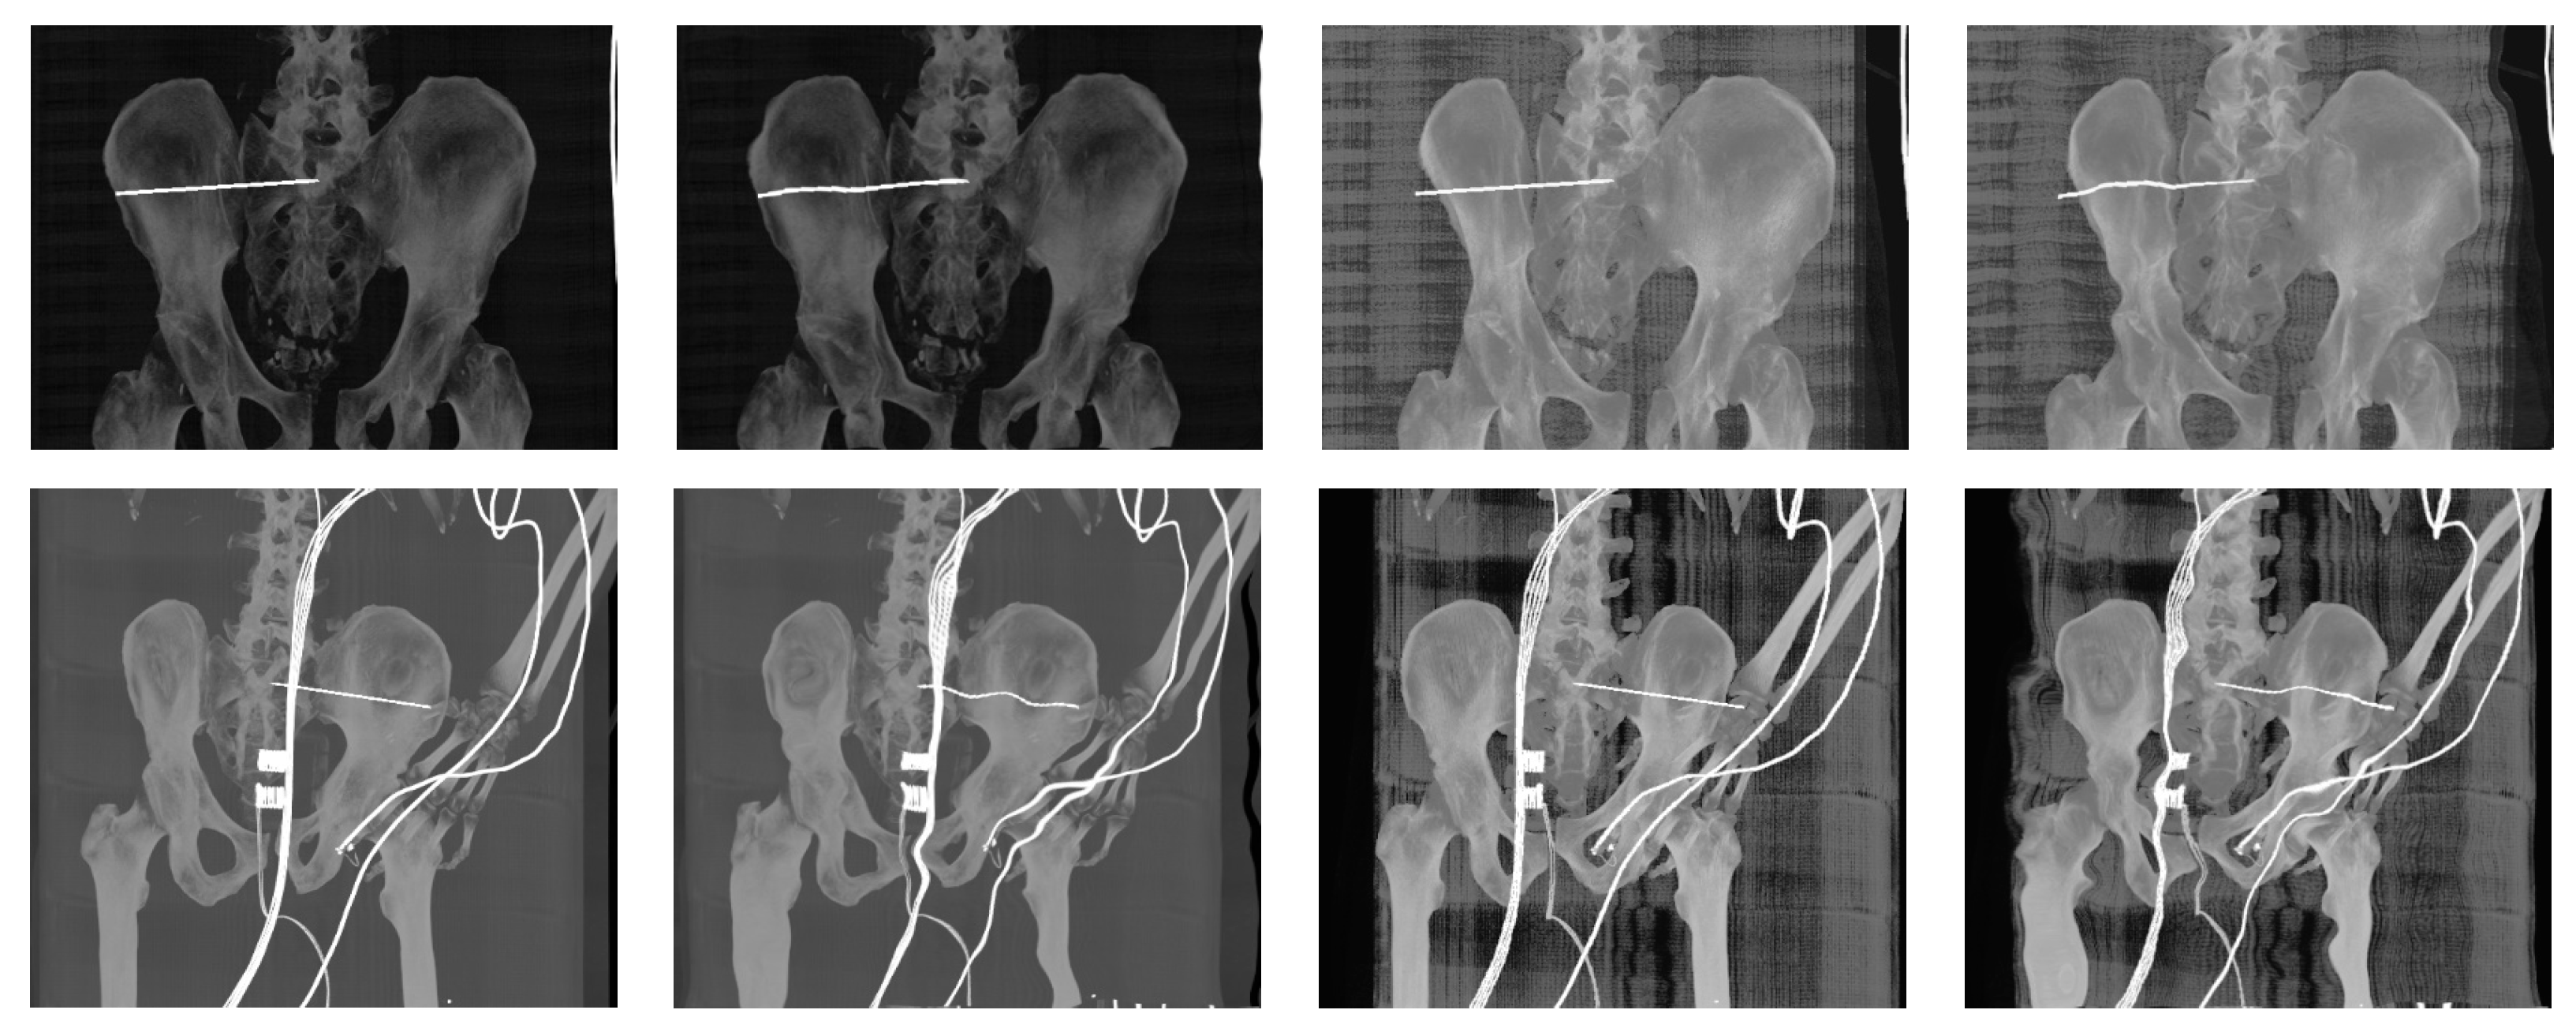

- Reconstructed DDR projections with virtual iliosacral screw

- Multimodal (X-ray/CT) image registration for optimal CT slice selection according to the reference X-ray image.

- Generation of digitally reconstructed radiograph (DRR) projections

- Multimodal image registration of DRR projections to a reference X-ray image